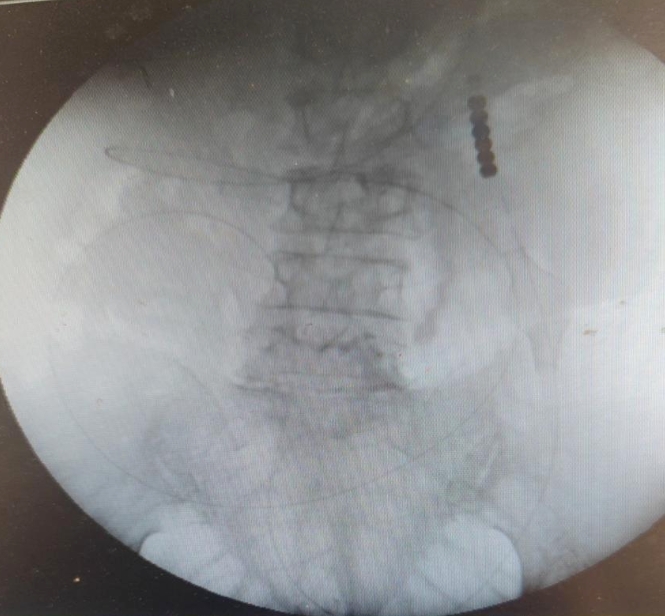

当晚,在雷冠东在DSA的精确引导下,成功将肠梗阻导管送入患者的空肠,并确保了导管位置的通畅性。术后,患者的腹痛、腹胀症状明显减轻,共引流出肠液约1000毫升。在近十天的的治疗过程中,伴随小肠导管及药物的推动,患者的小肠粪石逐渐向远端移动,11月2日最终顺利排出,患者的肛门排气排便恢复正常,复查结果显示无异常,整体恢复状况良好。 目前患者已恢复良好,康复出院。

此次手术的成功,标志着市一院胃肠外科在介入治疗领域又迈上了新的台阶。雷冠东介绍:“肠梗阻导管在DSA引导下放入空肠,可通过肠蠕动及重力共同作用,让导管像‘长眼睛’一样‘游入’小肠内,不断前进。同时,外置的负压吸引管,可不断吸引肠道内积存的废物及废气,反复用头端冲击肠梗阻处,直接抽吸减压,可降低肠腔内的压力,消除肠管水肿,缓解梗阻症状。可使某些高危的肠梗阻患者(例如高龄手术、病情复杂、合并症),多免于手术治疗,或者为高危患者的手术治疗创造更好的条件,赢得更长的术前准备时间,从而规避或降低治疗风险。”